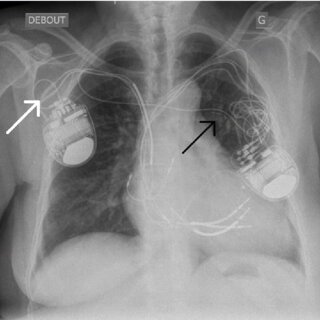

The Role of Pacemakers in Treating Atrial Fibrillation

A pacemaker is a small device placed in the chest or abdomen, and it helps manage abnormal heart rhythms. Doctors may recommend a pacemaker for